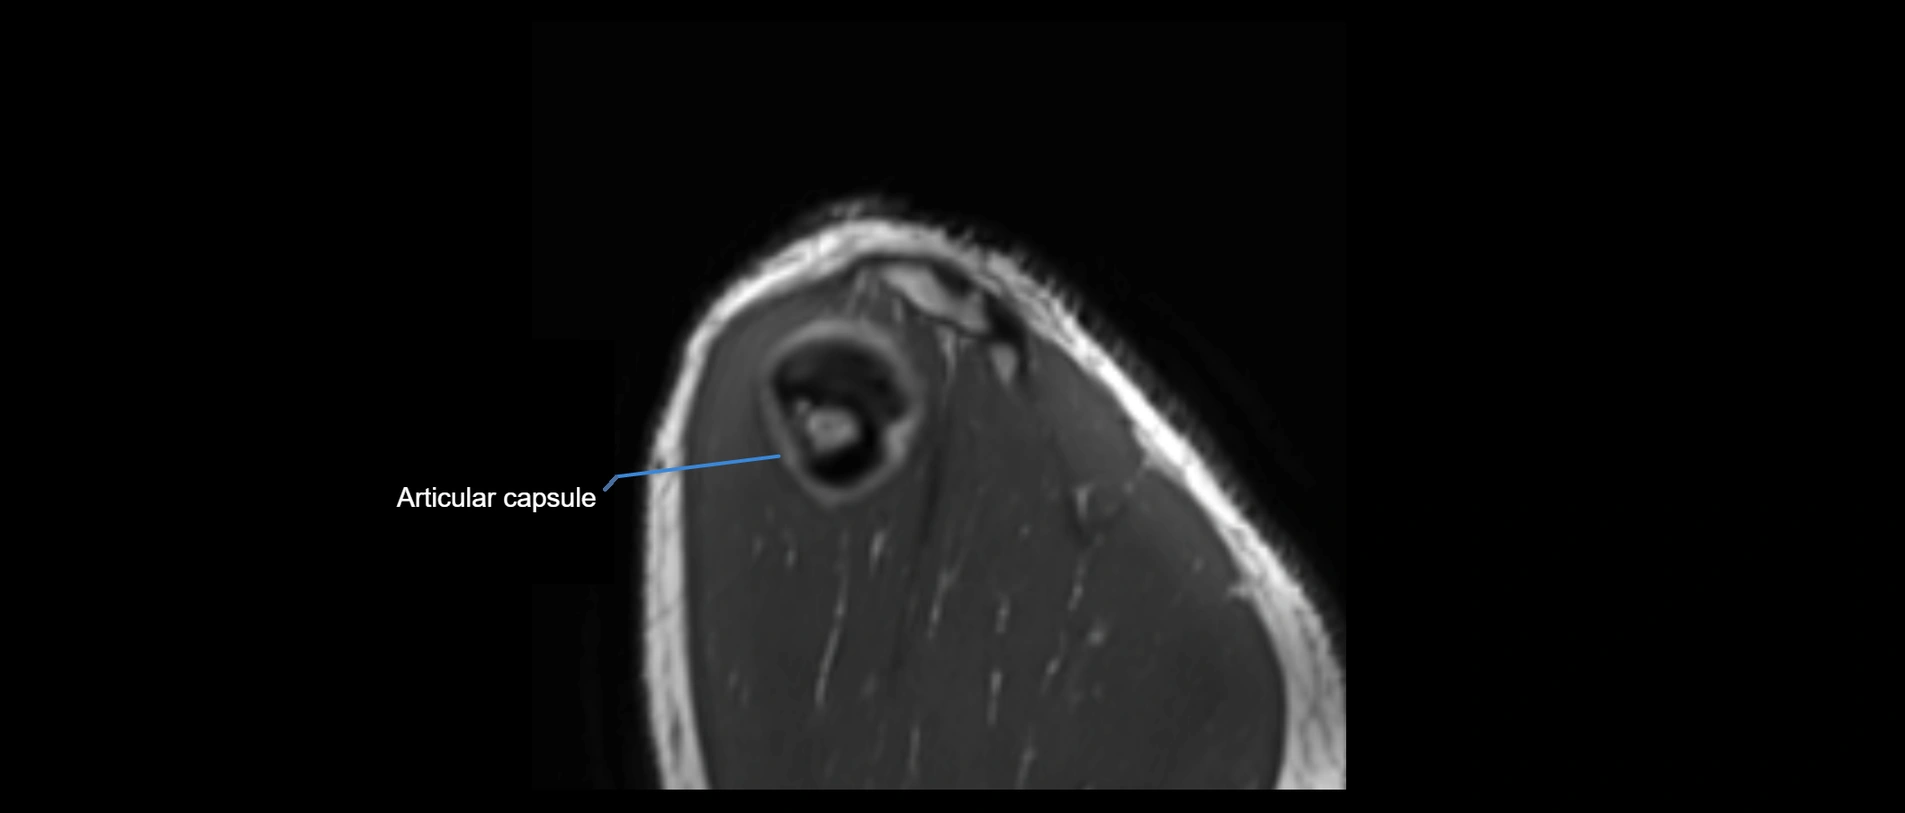

CT image

image